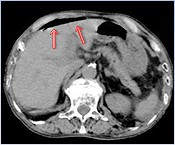

腹部CT検査

総胆管結石